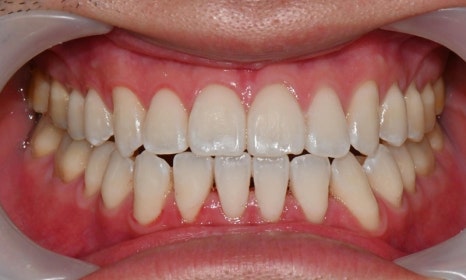

아래 앞니에 남아있는 레진 제거 후 미백 치료 결과

예전에 교정 치료를 마치고 미백을 하러 오시는 환자들을 보면, 가끔 브라켓을 뗀 이후 레진 접착제가 치아 표면에 일부 남아 있어서 그 부분이 노랗게 변색된 경우를 발견할 수 있습니다. 교정을 끝내고 브라켓을 제거한 이후에 레진 접착제를 깨끗하게 제거한 후 폴리싱을 해서 매끈하게 해주어야 하는데, 그렇지 못할 경우 남아있는 접착제에 의해 주변에 치태가 침착되거나 착색이 증가할 수 있고, 남아있는 레진이 변색될 수 있습니다. 이 경우 남아있는 레진을 제거한 후 미백을 해주게 되면 깨끗한 치아를 얻을 수 있습니다.